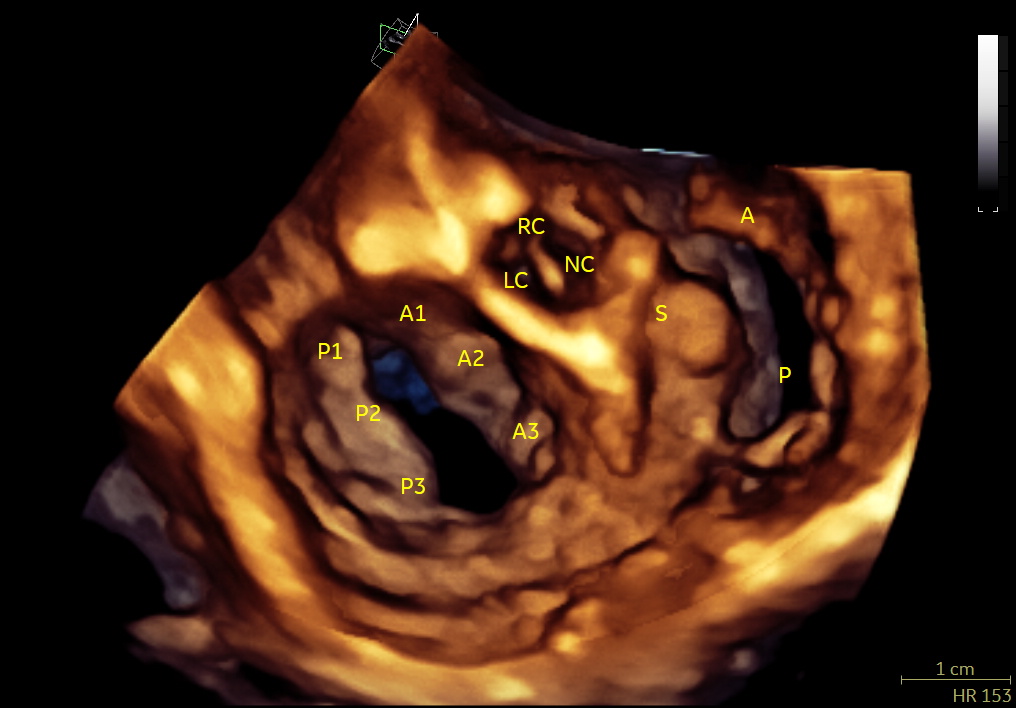

- ecocardiografia standard (modalità M-mode, 2D, Doppler, TDI, Strain e STE) e 3D;

- ecocardiografia transesofagea;

- Studio ecocardiografico 3D delle valvole cardiache nel cane